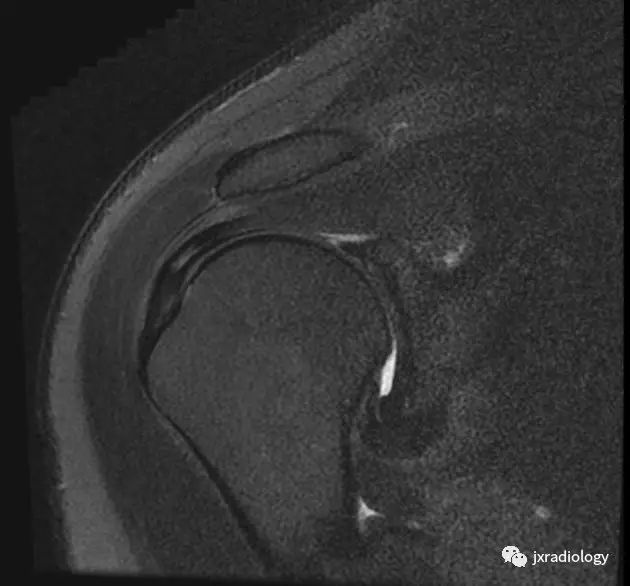

MRI关节囊造影提示腋囊体积缩小:

其他MR关节造影包括

• 喙肱韧带(CHL)增厚

• 喙突下三角征

• 腋囊正常容量15-18ml,本病小于10ml,多数小于5ml(文献上)